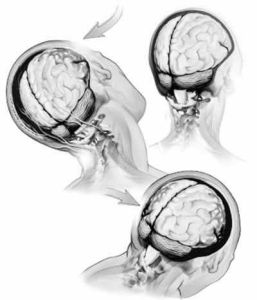

腦外傷示意圖疾病病因

不同病因1.直接損傷:

(1)加速損傷:即運動著的物體撞擊於靜止狀態的頭部所發生的腦損傷,如棍棒或石塊擊傷。

(2)減速損傷:即運動著的頭部撞碰到靜止的物體而致傷,如墜落和跌傷。

(3)擠壓傷:即兩個不同方向的外力同時作用於頭部,使顱骨變形致傷。